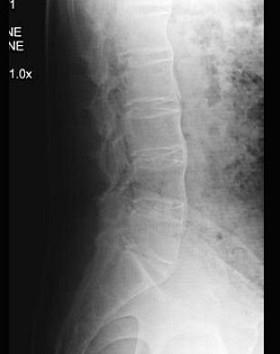

问题 41岁男性患者,发现腰部酸肿不适10多年,近来年感病情加重,腰部活动受限,晨起腰部僵直1年,行腰椎正侧位摄片如图示,最佳的诊断是 ( )

选项 A、斯梯尔综合征 B、化脓性脊柱炎 C、弥漫性骨质增生症 D、强直性脊椎炎 E、腰椎退行性变

答案 D